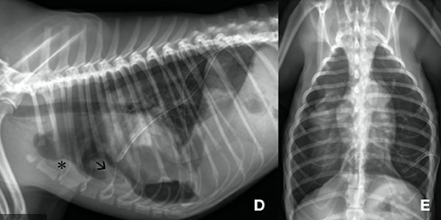

개념적으로 이야기 하자면 전통적인 흉관 튜브와 1way jar를 이용한 공기 제거를 하는데 이때 동종 혹은 자신의 혈액을 수혈하듯 흉강에 주입해주면

이 혈액이 구멍난 폐야를 덮어 fibrin이나 혈괴로 막히게 될고 흉관 튜브를 삽입하고 있는 기간을 줄일 수 있다는 발상이다.

이 증례에서는 폐야의 bulla가 파열하여 생긴 spontaneous pneumothorax 환자에서 사용한 예시라서 한번쯤 참고할만하다.